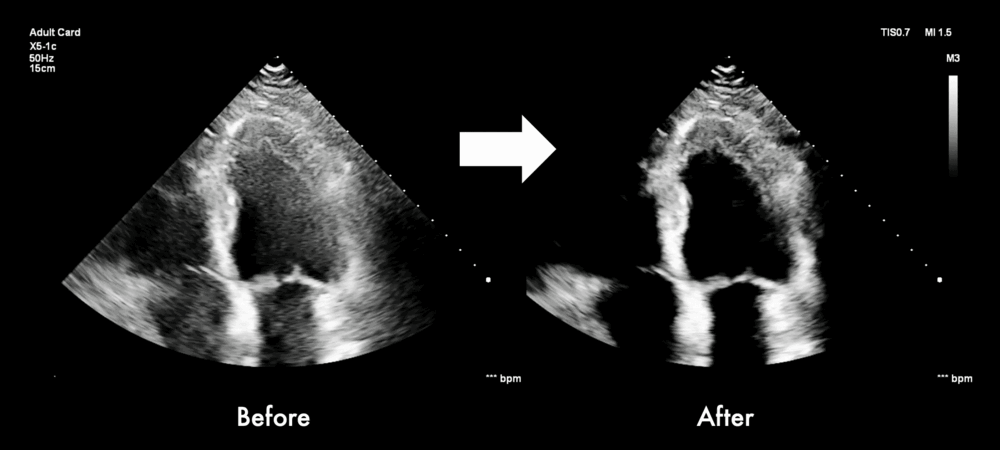

Stevens bladert in zijn proefschrift en toont verschillende echobeelden van een hart. “Met dit nieuwe model zien we een duidelijke kwaliteitsverbetering van de echobeelden. Ook voor complexere echografie, zoals bij het groeiende aantal obese patiënten.”